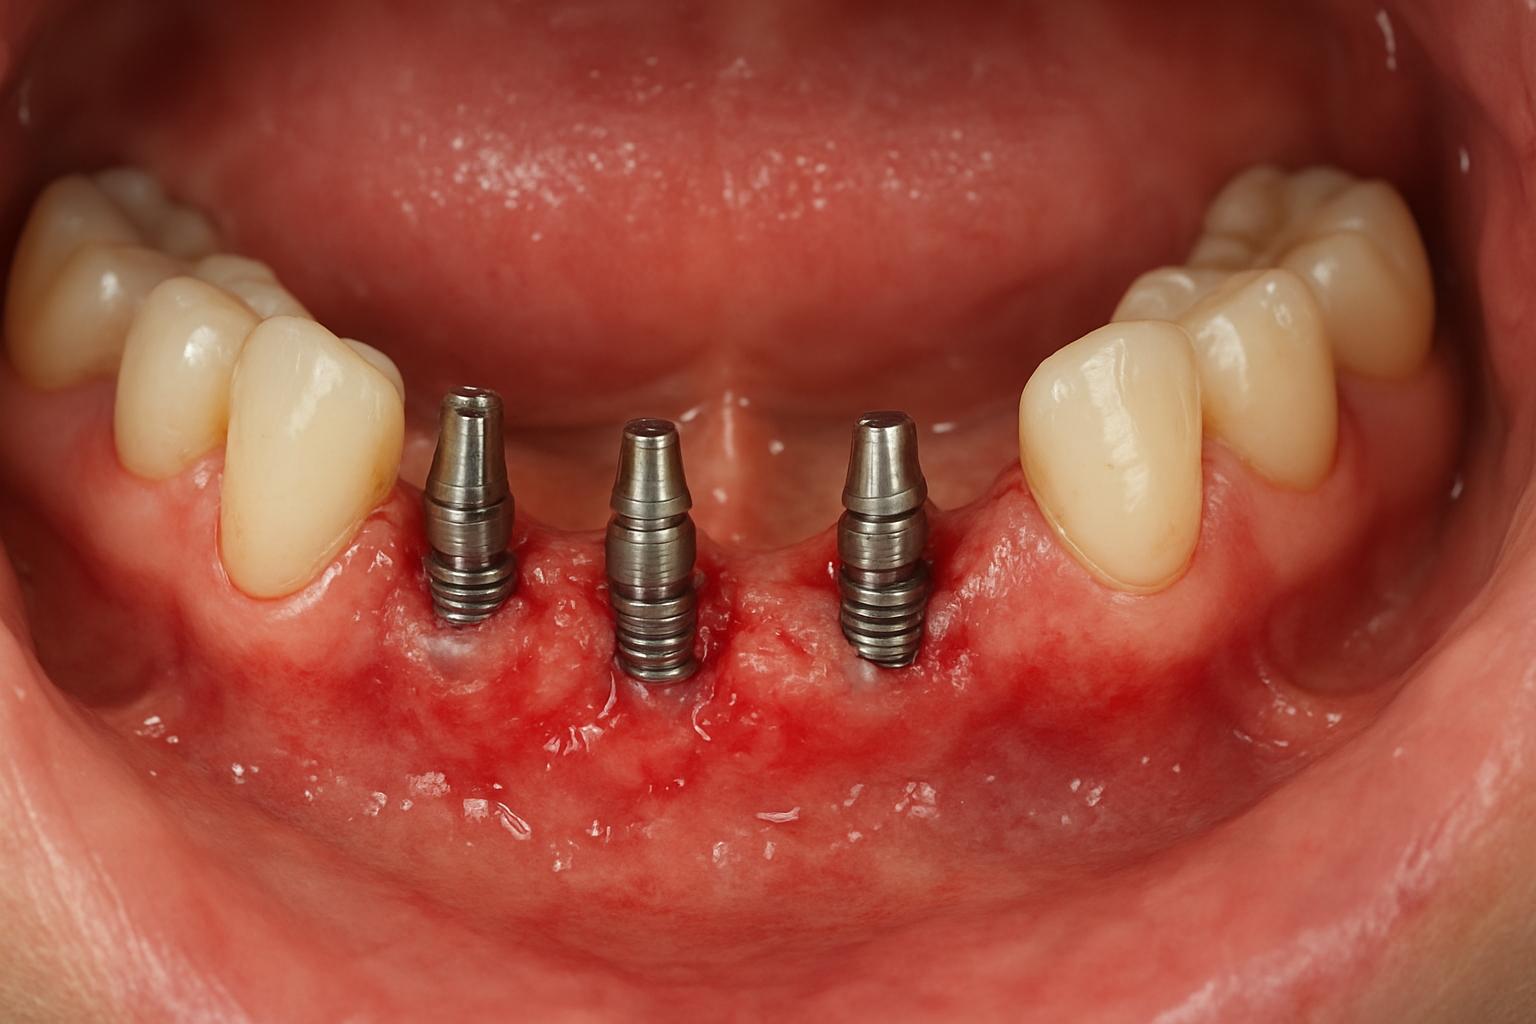

Базальная имплантация — это способ установки зубных имплантов с фиксацией в кортикальном слое кости, то есть в плотной, внешней «плите» челюсти. Главное отличие от классической схемы в том, что опора берётся не из рыхлой губчатой кости альвеолярного отростка, а «зацепляется» за более твёрдую костную ткань. Это даёт высокую первичную стабильность и позволяет ставить временные протезы сразу или в очень короткие сроки.

Такие импланты чаще всего бывают одночастными с гладкой полированной шейкой и специальной формой тела, рассчитанной на механическую фиксацию в нескольких кортикальных слоях. Благодаря этому не всегда требуется предоперационное наращивание кости, что особенно важно при выраженной атрофии челюсти.

- Операция — установка базальных имплантов, при необходимости удаление оставшихся зубов или санация очагов инфекции.